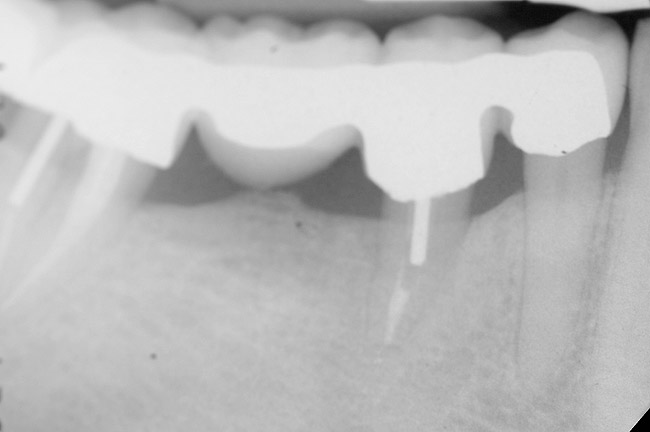

Figure 9  Extraction of teeth Nos. 29 and 31 with immediate implants (Straumann USA, Waltham, MA) placed into the site.

Figure 9

Figure 10  Implants seen in Figure 9 restored approximately 3 months after placement.

Figure 10

Figure 9 shows the implant placement at the time of extraction and Figure 10 shows the implant-supported fixed bridge. In one surgical procedure, the implants in the Nos. 29 and 31 positions were placed at the time of the extraction of these two teeth. The implants were restored approximately 3 months after placement.